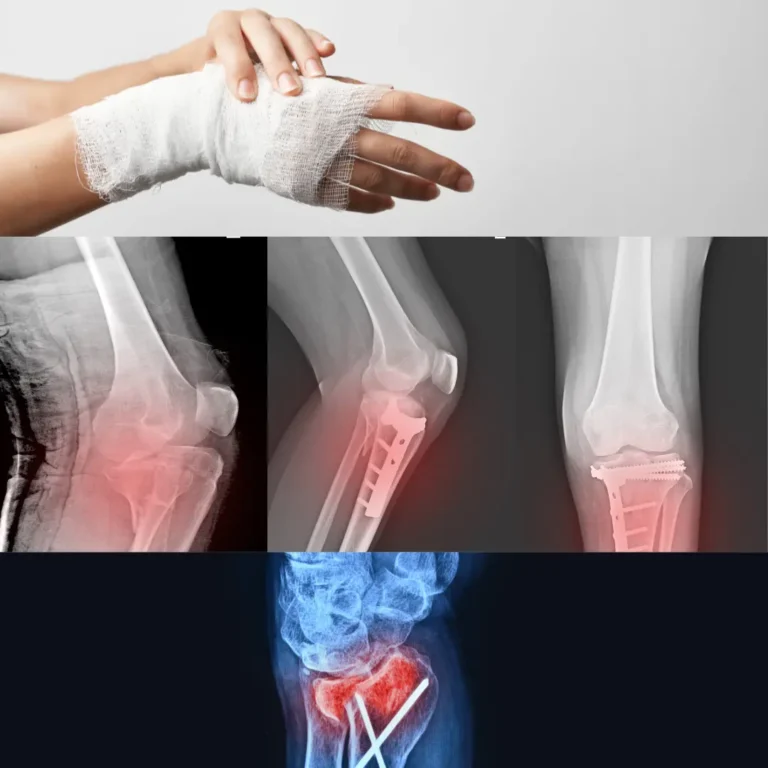

At SreeRam Hospitals, Vijayawada, our Orthopedics Department is dedicated to providing world-class care for patients suffering from musculoskeletal disorders, injuries, and degenerative conditions. With a team of highly skilled orthopedic surgeons, advanced diagnostic technologies, and state-of-the-art treatment protocols, we ensure personalized care to restore mobility, relieve pain, and improve quality of life.

Trauma & Fractures

Complex fractures

Dislocations

Accident-related injuries